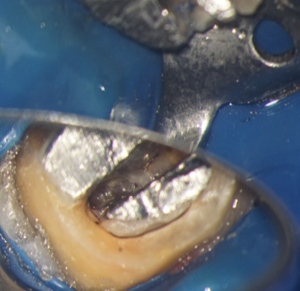

Pivotul de metal este voluminos și cimentat în două dintre canale și în perforație, așa că trebuie segmentat pentru a fi îndepărtat (Fig. 4.12.5, Fig. 4.12.6, Fig. 4.12.7).

După îndepărtarea unui segment din pivot, vedem cavitatea artificială care traversează grosimea dintelui, până în țesutul de susținere (Fig. 4.12.8). În țesutul de susținere se observă un material albastru, gumos. Este cel mai probabil un material din clasa silicaților, folosit pentru amprentarea spațiului din interiorul dintelui pentru confecționarea pivotului metalic (Fig. 4.12.9). Reușim să îndepărtăm o parte a acestui material și închidem perforația folosind un ciment bioceramic (MTA) (Fig.4.12.10, Fig. 4.12.11).